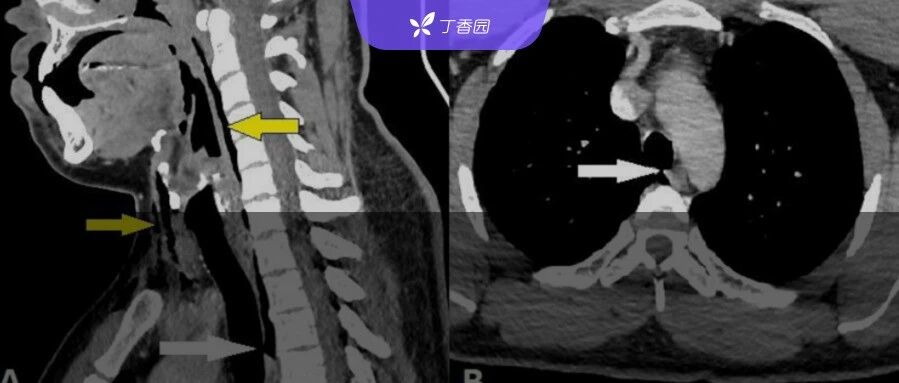

| 全球首例!BMJ 报告:因为憋了个喷嚏,气管穿孔被送进急诊... | 查看 | 2023-12-15 12:15:27 | 14474 | 12 | 2023-12-15 13:17:11 | 丁香园 | |